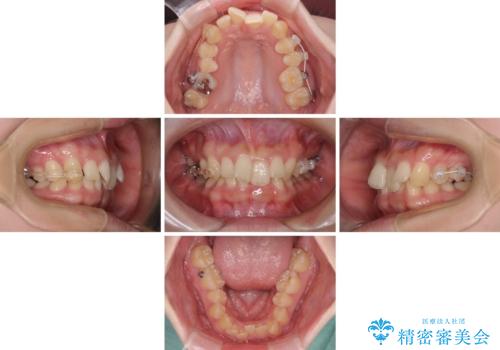

奥歯の咬み合わせを改善しながら、並行してインビザラインで歯列を整えることとしました。

カリエールディスタライザーやワイヤー矯正を併用したことで、確実かつ短期間で治療を終えることができました。